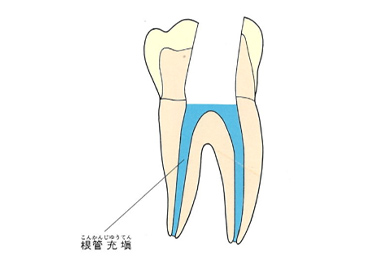

神経を取ったらそれで治療が終了ではありません。

その後神経があった管の中にばい菌が侵入しないように薬を詰めていきます。普通はガッタパーチャポイントと呼ばれる材料とシーラーという薬剤を併用して根管(コンカン)を封鎖します。

水色の部分がガッタパーチャポイントとシーラーです。

ガッタパーチャポイントです。この薬とシーラーを根の中に入れていきます。

抜髄まとめ

虫歯で痛くなると抜髄をします。抜髄して神経をきれいに取った後、ガッタパーチャポイントとシーラーを根管内に入れて根管を封鎖します。ここまでが歯髄炎という病気の治療です。この後は土台を作り、型取りをして冠を被せてその歯の治療は終了です。

ガッタパーチャポイントは、理想的には歯根(シコン)の先ピッタリが良いと言われています。

しかし先ほど説明したように根管(コンカン)の形態は非常に複雑怪奇です。なので一概にピッタリが良いと限らないケースもあります。

ここでは一応、根尖(コンセン)付近が良いということにしておきましょう。

上の図にあるように神経の管に入れる薬が根尖(コンセン)まで入っていなかったり、途中までしか入っていなかったり、薬がスカスカだったりするとその空間にばい菌が繁殖して感染を起こします。

そうすると神経を取ったはずなのに、その後歯ぐきが腫れて痛くなるのです。

この根っこの病気を根尖性歯周炎というのです。そしてこの根尖性歯周炎を治すことを感染根管治療と言います。